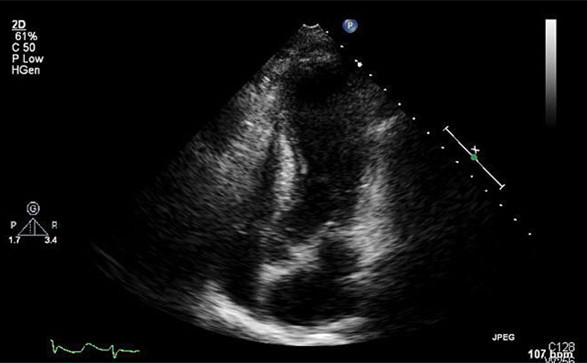

经胸超声心动图是诊断TCM室壁运动异常的快速方式,特别是诊断LV运动减低或心室中部和心尖部的运动缺失。这些室壁运动异常超出了任何单一冠状动脉的分布区域。左室射血分数(LVEF)可以通过超声心动图、CMRI或左心室造影来估算。

超声心动图显示,TCM患者心尖部在收缩期无运动,射血分数为40%。